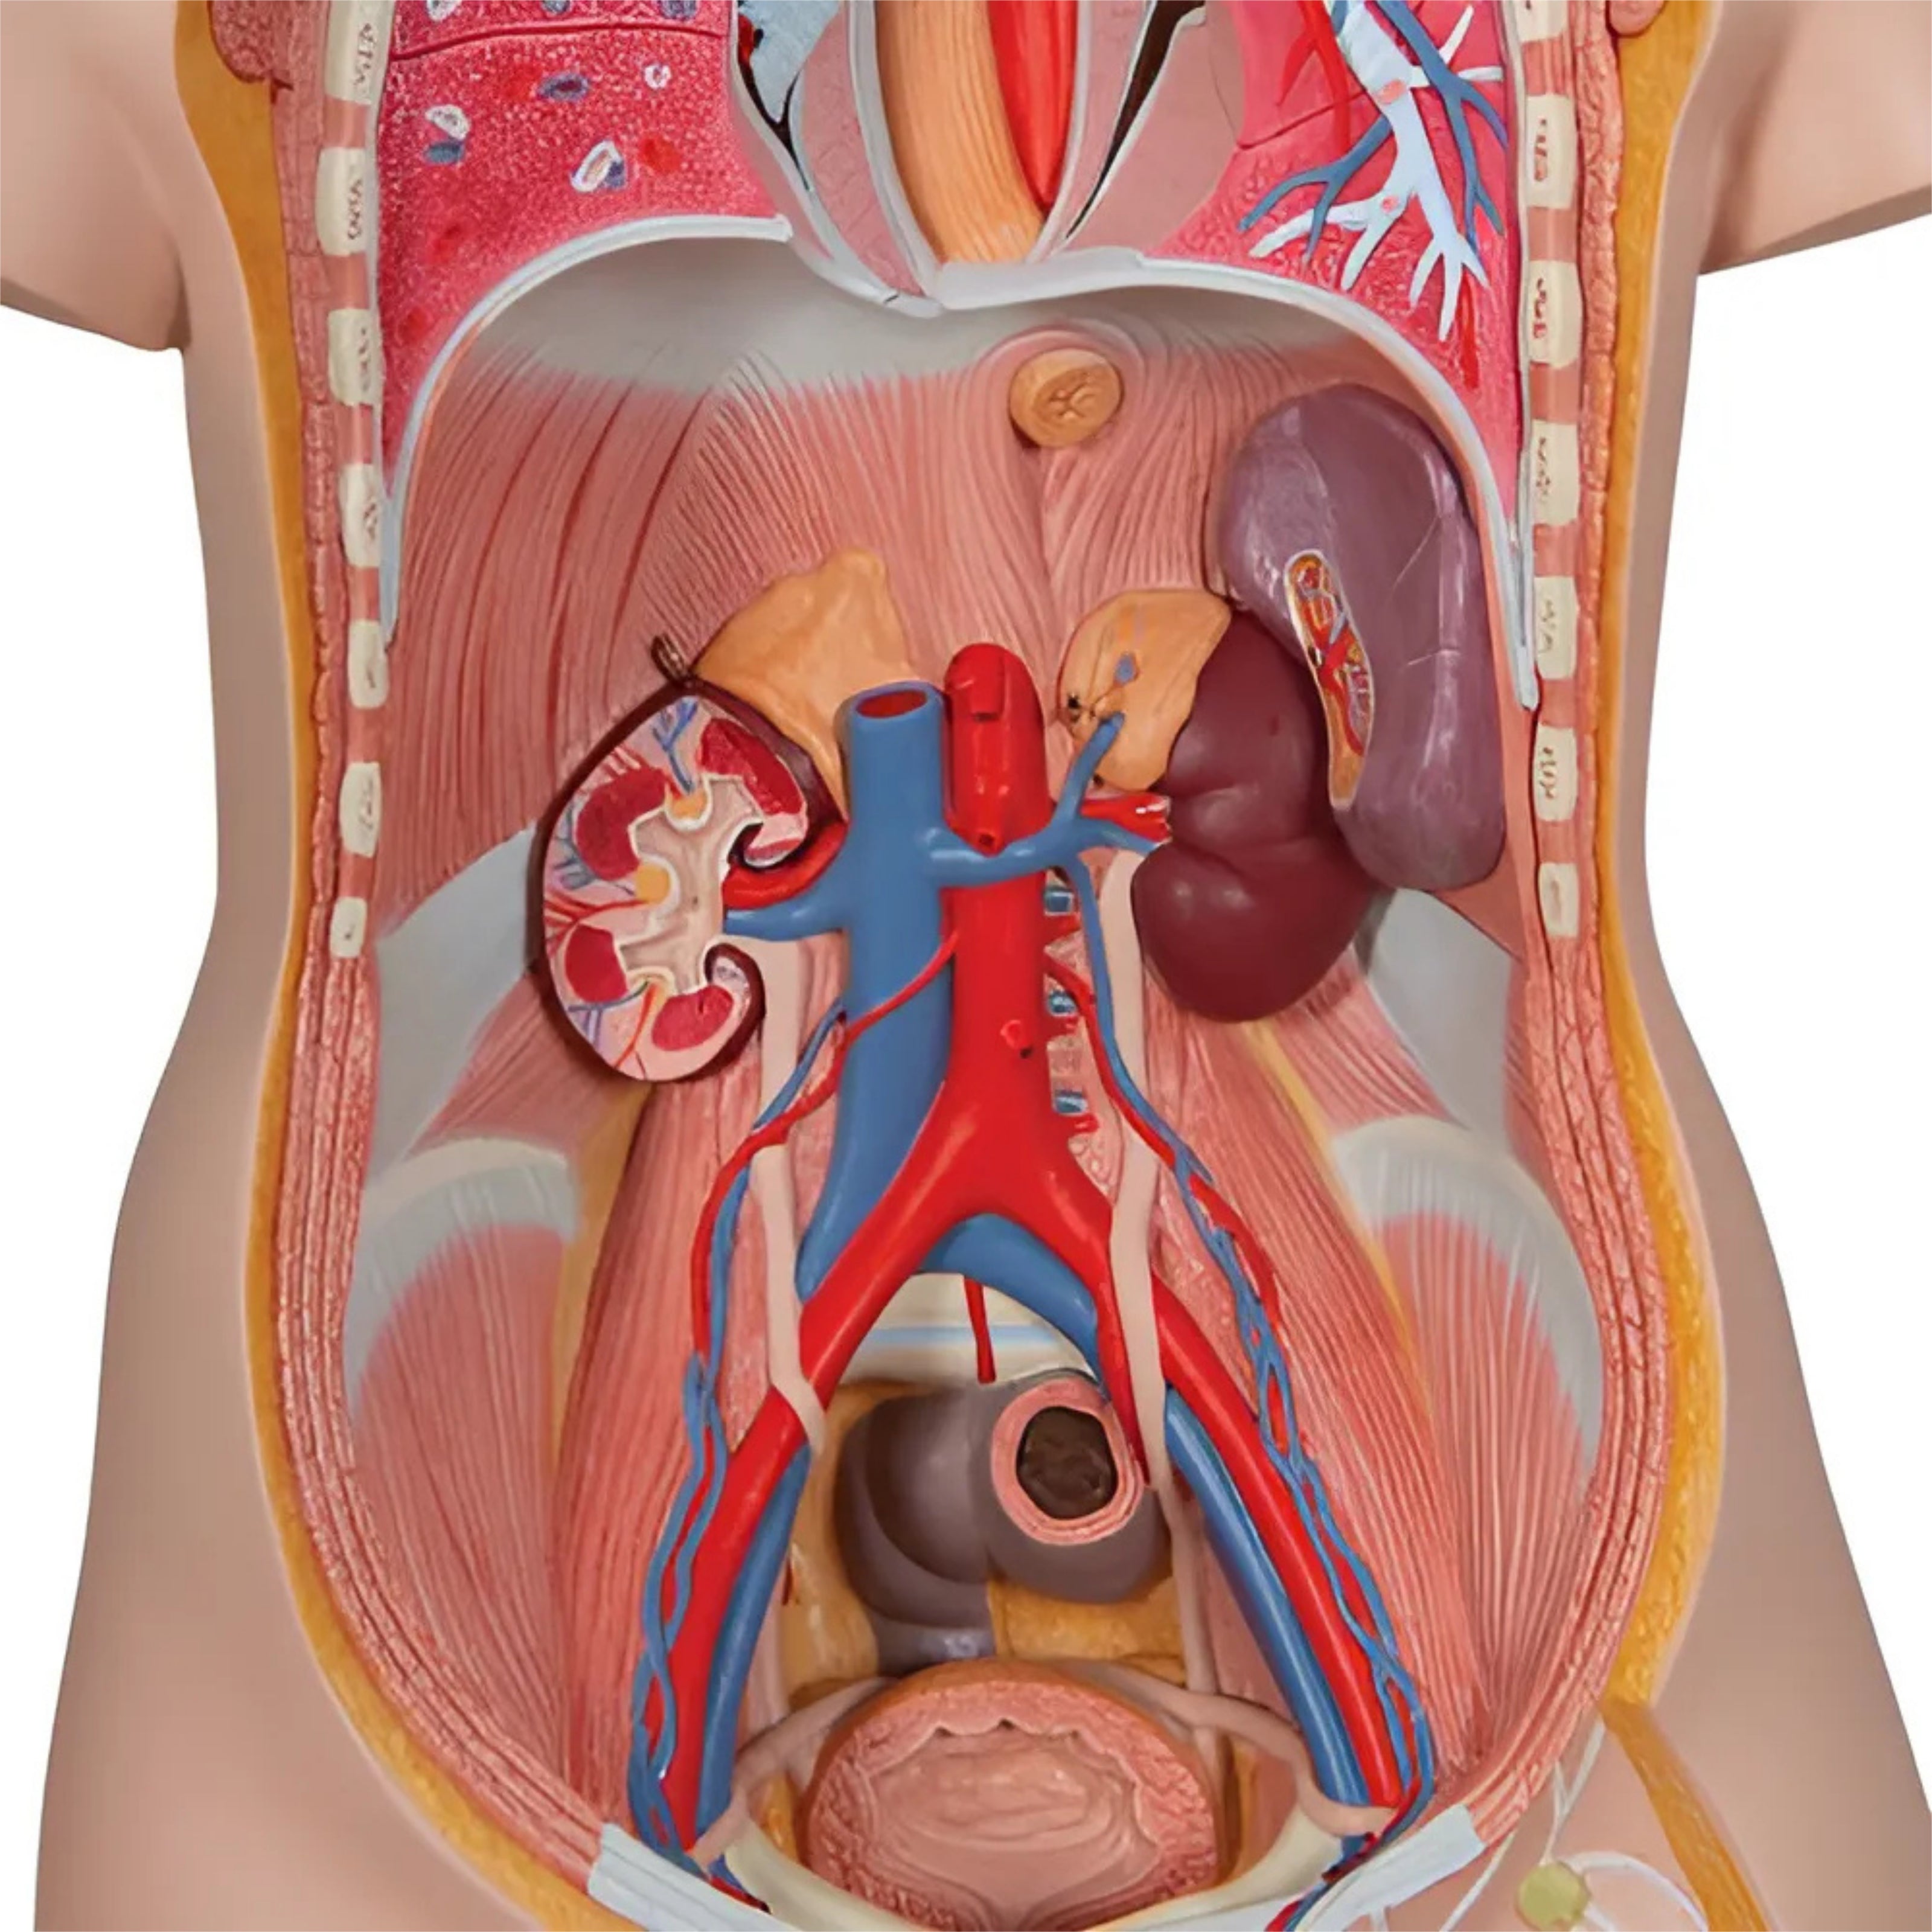

Riñones con Órganos Posteriores del Abdomen Superior (3 Piezas) - 3B Smart Anatomy

Precio de venta$12,993.33